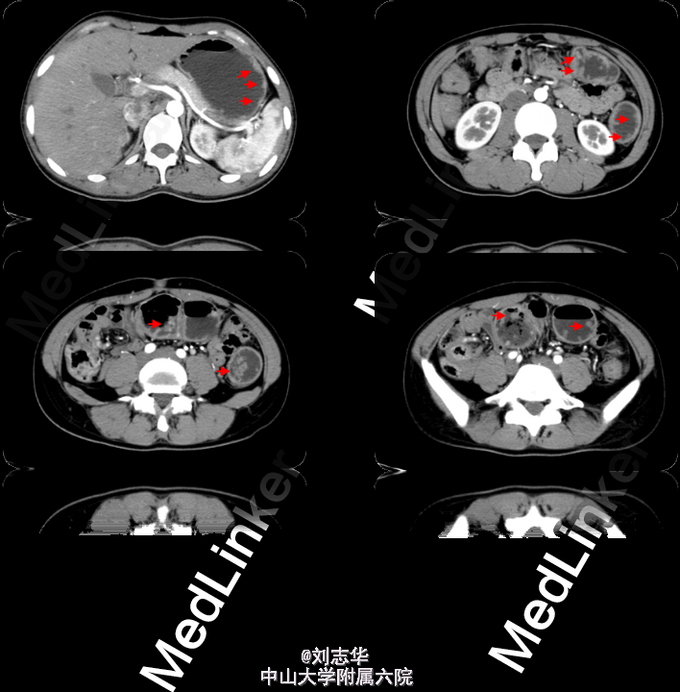

专科检查:腹壁平坦,呼吸运动正常, 无皮疹、条纹、疤痕、包块,无腹壁静脉曲张,未见胃肠型及蠕动波。 腹软,无压痛、无反跳痛、腹部肿块未触及。肝脾肋下未触及,肝区双肾区无叩痛,腹部移动性浊音阴性,肠鸣音正常,4次/分。肛检: 左侧卧位:肛门指检可及直肠多个小肿物,大小约0.2-0.5cm,表面光滑,指套无血染。 肠镜:全结直肠多发息肉(数目大于100枚);痔。 胃镜:胃多发息肉。 胸腹盆增强CT:胃内、所示左半横结肠-直肠弥漫多发息肉。

诊断:FAP 行手术治疗:腹腔镜全结直肠切除 + 回肠储袋肛管吻合 + 回肠造瘘术。